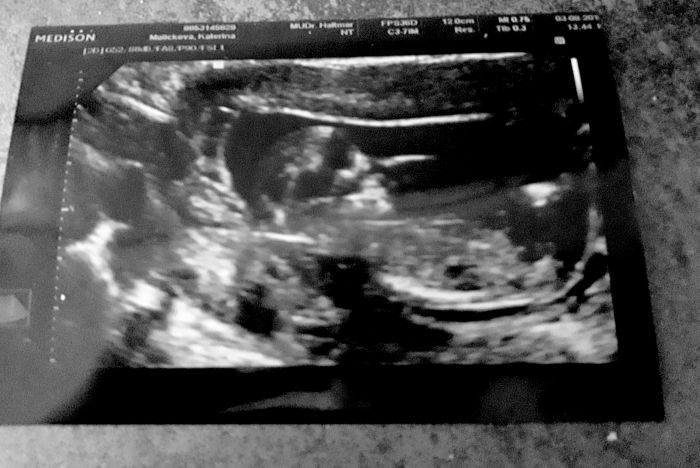

Jinak ještě k mé včerejší kontole, vkládám fotku

všechny měřené hodnoty byly ukázkové (NT,nosní kůstka,čelistní úhel,páteř,prstíky) ,miminko nám mávalo